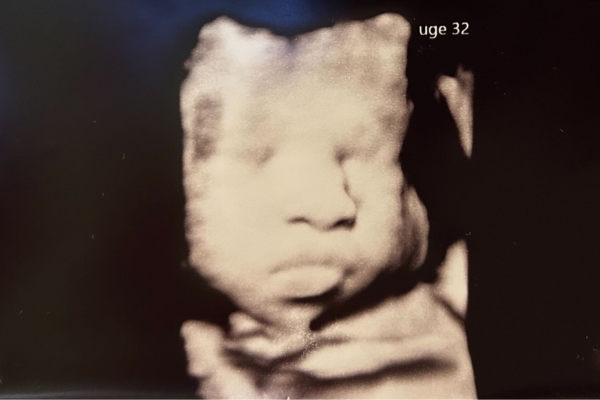

Gravid uge 32

Uge 32+0 – 32+6

Nu går det stærkt med tilvæksten. Din baby vejer nu omkring 2000 gram, og måler cirka 42 cm. På dette tidspunkt vil 96 % af alle børn ligge i hovedstilling. Det betyder, at hovedet vender nedad i livmoderen. Hovedet er det tungeste sted på barnet, og for at udnytte pladsen optimalt, drejer barnet sig med hovedet nedad. Tyngdekraften spiller også en rolle, i at hovedet pga. tyngden søger ned. Suttereflekserne er ligeledes aktive og bliver brugt på at sutte på de små fingre. På en scanning vil du kunne se, hvordan den lille sutter på fingre og hænder, eller hvordan barnet drikker fostervand og tungen bevæger sig op og ned, når vandet synkes. Scanningsbillederne viser, hvordan der er fostervand i mavesækken og i barnets urinblære. Man kan altså se, at drikke-, synke-, tissefunktionen fungerer.